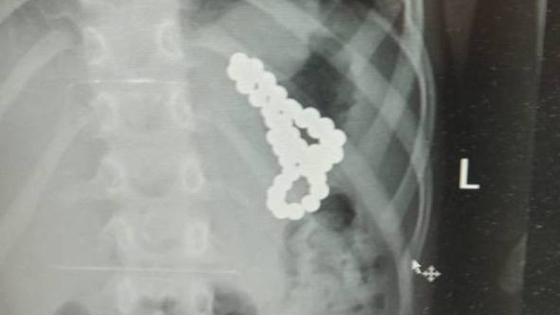

Взрослые отвезли ребенка в больницу, однако думали, что их дочь просто переутомилась в долгой дороге. Но все оказалось иначе: девочка призналась, что проглотила несколько деталей магнитного конструктора, который ей купили родители перед поездкой. Она "съедала" по одному шарику, потому что, заявила сама москвичка, ей было скучно.

Врачи провели операцию и достали из желудка юной пациентки 46 магнитов. В настоящий момент, как сообщает Telegram-канал Baza, девочка выписана и чувствует себя хорошо.